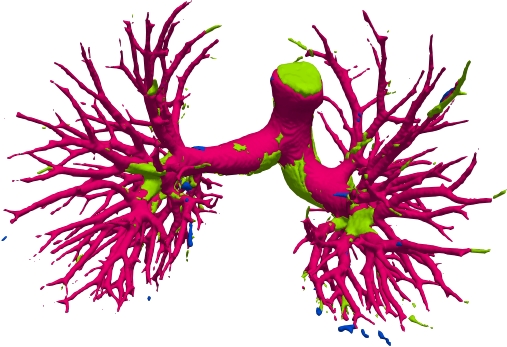

We qualitatively analyze our method on four challenging lung organ datasets. In Fig. 5, SFCN [19] suffers from severe false positives and some false negatives, especially for the big green areas of airway leakages. WNet [22] is mainly influenced by false negatives on the main trachea. For the Fibrosis dataset at the third row, it also encounters the false negative problem in the terminal bronchioles moderately. FANN [10] bears the slight discontinuity issue of false negative in the terminal bronchioles of BAS dataset, and the severe discontinuity and airway leakage problems on the more challenging Fibrosis benchmark. Instead, due to the above two novel modules, our method can solve the defects of false negative, discontinuity, and leakages faced by past advanced methods. Besides, the results on PARSE22 artery dataset in supplementary Fig. 6 also proves this.